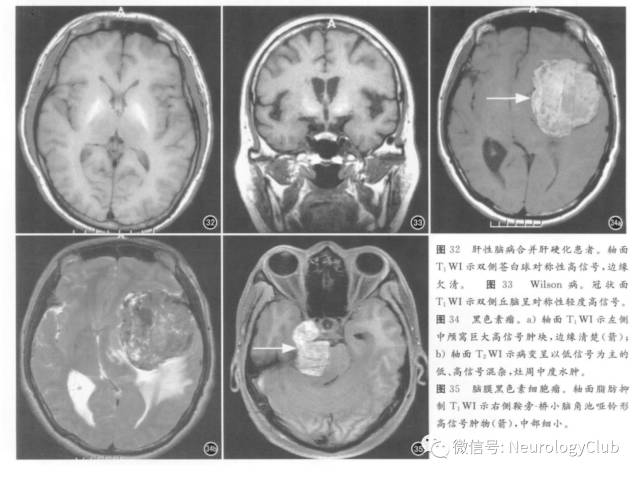

慢性肝病、自发性与医源性门-体静脉分流(后者包括经颈静脉门体静脉分流即TIPS)均可出现脑内T1WI高信号,机制尚不完全明确,可能为锰过度沉积所致星形细胞氨解毒效应,铜沉积也增多,但铜并非顺磁性物质。正常情况下,锰经胃肠道吸收、胆道系统排泄。肝细胞功能障碍时,血液内锰含量增高,病理学上可见星形细胞增生。MRI信号各异,特征性表现为T1WI高信号及T2WI等或低信号,见于基底核、下丘脑、四叠体板、红核周围、大脑脚、内囊、垂体前叶、胼胝体、齿状核等,半数以上为双侧性与对称性(图32)。肝移植后此种T1WI高信号可消退。鉴别诊断主要是其他引起双侧性基底核短T1信号的病变,包括甲状旁腺功能低下及假性甲状旁腺功能低下、Fahr病、缺血缺氧性脑病、非酮症性高血糖、错构瘤、神经纤维瘤病I型、日本脑炎伴出血等,这些疾病特点是伴脑实质其他部位病变或T2WI异常信号。其他可引起脑内锰过度沉积的原因包括长期胃肠外营养、先天性肝内门-体静脉分流、焊工、肝功能障碍患者反复使用MR对比剂锰福地匹酸钠等。

2. Wilson病

1. 黑色素瘤

也称恶性黑色素瘤,可为颅内原发或颅外黑色素瘤转移。原发者来源于软脑膜黑色素细胞小泡或蛛网膜黑色素细胞,可发生于颅内和脊髓硬脊膜的任何部位。MRI表现取决于瘤内黑色素含量和瘤内是否出血。典型表现为T1WI高信号与T2WI低信号(图34),其原因是黑色素的自由基含有不成对电子和氢质子的顺磁性效应,二者相互作用导致T1和T2弛豫时间缩短。根据黑色素含量不同分为黑色素型(T1WI高信号与T2WI低信号)、不含黑色素型(T1WI低或等信号、T2WI加权像呈中高或等信号)、混合型(信号混杂,既有T1WI高信号,也有等信号与稍低信号,T2WI以高信号为主,也见少量低信号)及血肿型(类似于自发性脑出血)。平扫T1WI等信号或稍高信号增强扫描时部分强化明显。鉴别诊断主要是亚急性颅内血肿、胶质瘤与转移瘤伴出血,星形细胞瘤或转移瘤出血CT与MRI表现为不均质肿块,占位效应及水肿可均较明显,转移瘤常有原发瘤史。

2. 脑膜黑色素细胞瘤

为脑膜缓慢生长的色素性良性病变,见于后颅凹、Meckel腔、鞍区、松果体区、椎管,尤以脑干腹侧常见。病理学特征为肿瘤细胞无间变、坏死及周围组织侵犯,可见较多黑色素小体及前黑色素小体,T1WI为等或高信号(图35),T2WI为等或低信号。T1WI高信号部分并非脂肪,在脂肪抑制序列上仍为高信号。增强扫描肿瘤呈均匀或不均匀强化。鉴别诊断包括合并出血的三叉神经鞘瘤、脑膜瘤、海绵状血管瘤及表皮样囊肿。